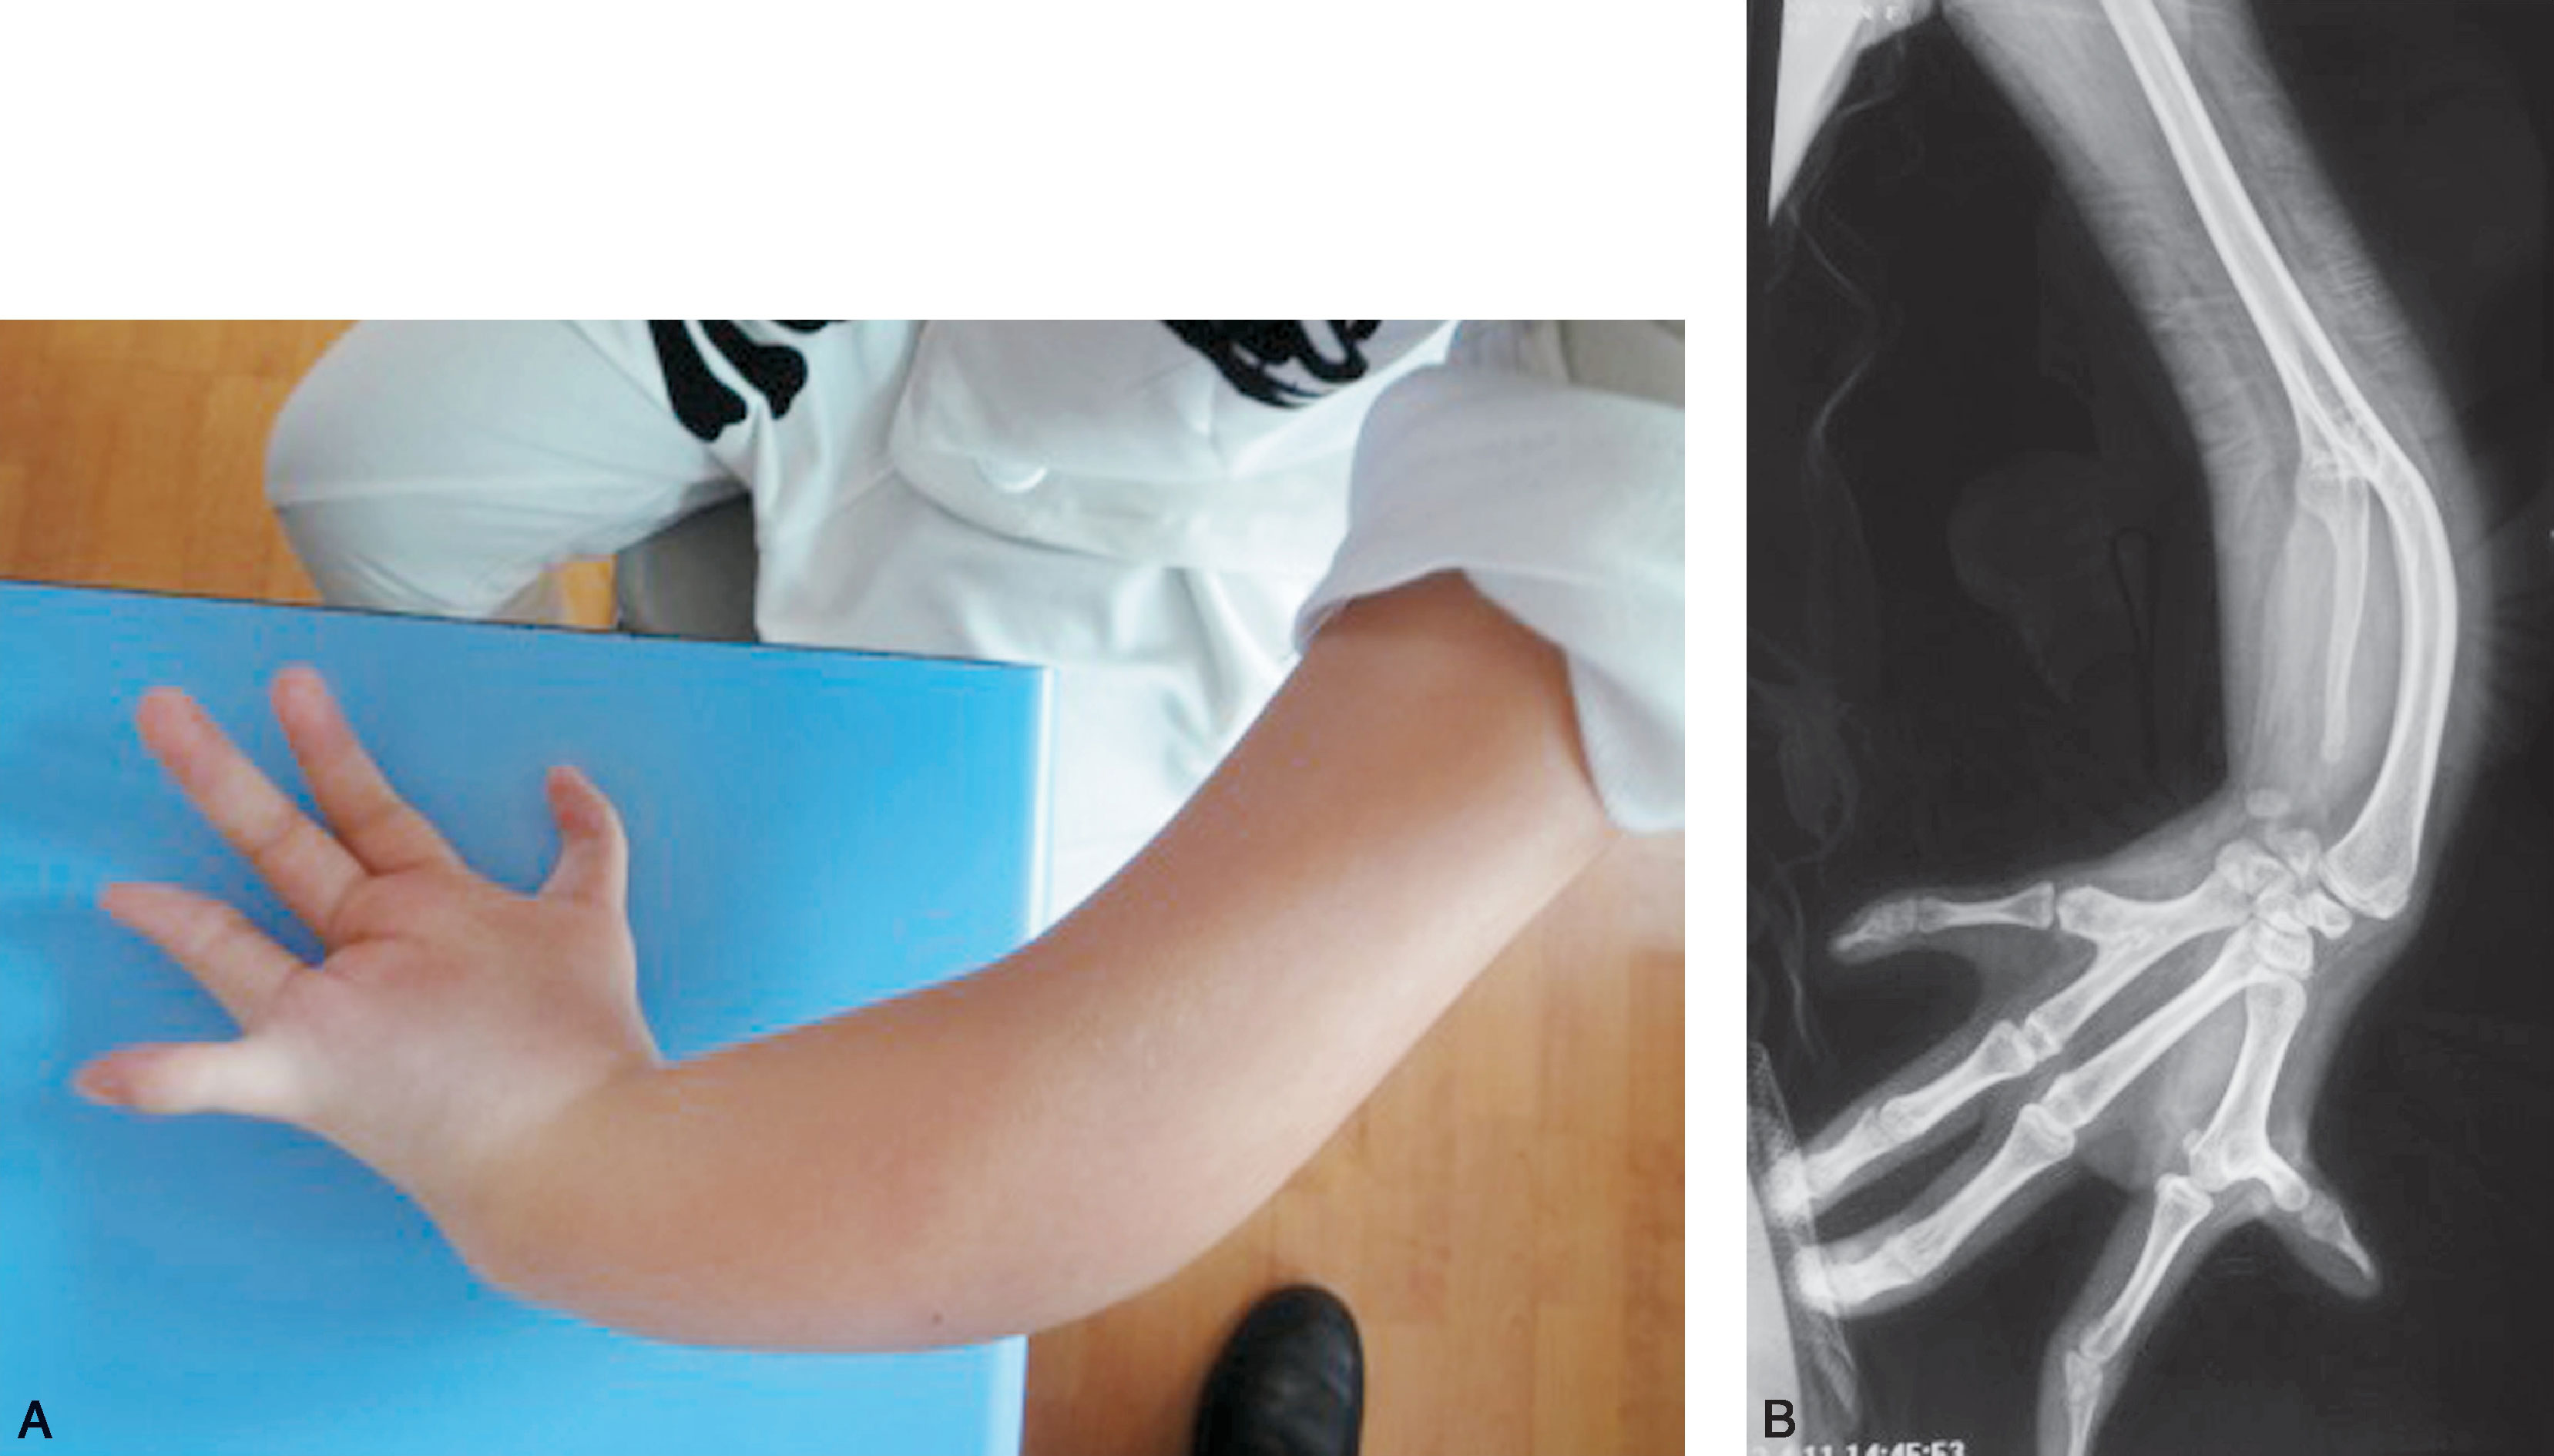

图1-2-21 全肘关节骨性融合病例

A.左侧前臂尺侧纵列发育不良;B.X 线片显示左侧肱骨桡尺骨融合(全肘关节融合),合并尺骨发育不良(尺骨远端部分缺如),桡骨继发性侧弯,第Ⅰ、Ⅱ及第Ⅳ、Ⅴ掌骨融合